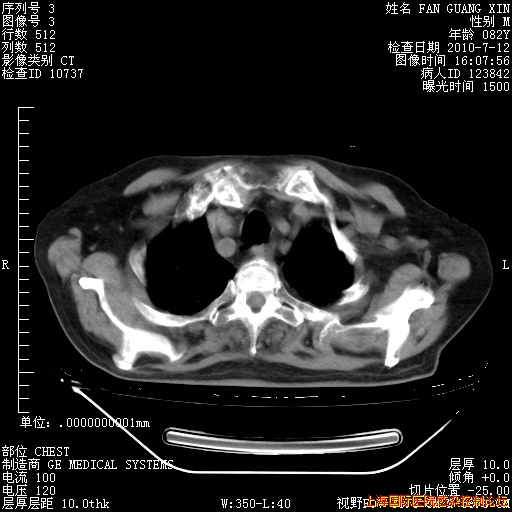

今天复查CT

今天CT

整整相隔30天的肺部CT好像有所好转啊。甲强龙减量第3天,需要观察体温。

海管,自昨日你和我通完话后,不知您岳父消化道症状有无缓解?体温怎样?阅读7.12日胸部ct,个人认为目前激素治疗是有效的,甲强龙减量是适宜的。因在抗痨治疗,需密切观察肝功、肾功能和血常规。不过,老年、长期住院和大量使用激素,很担心菌群失调发生